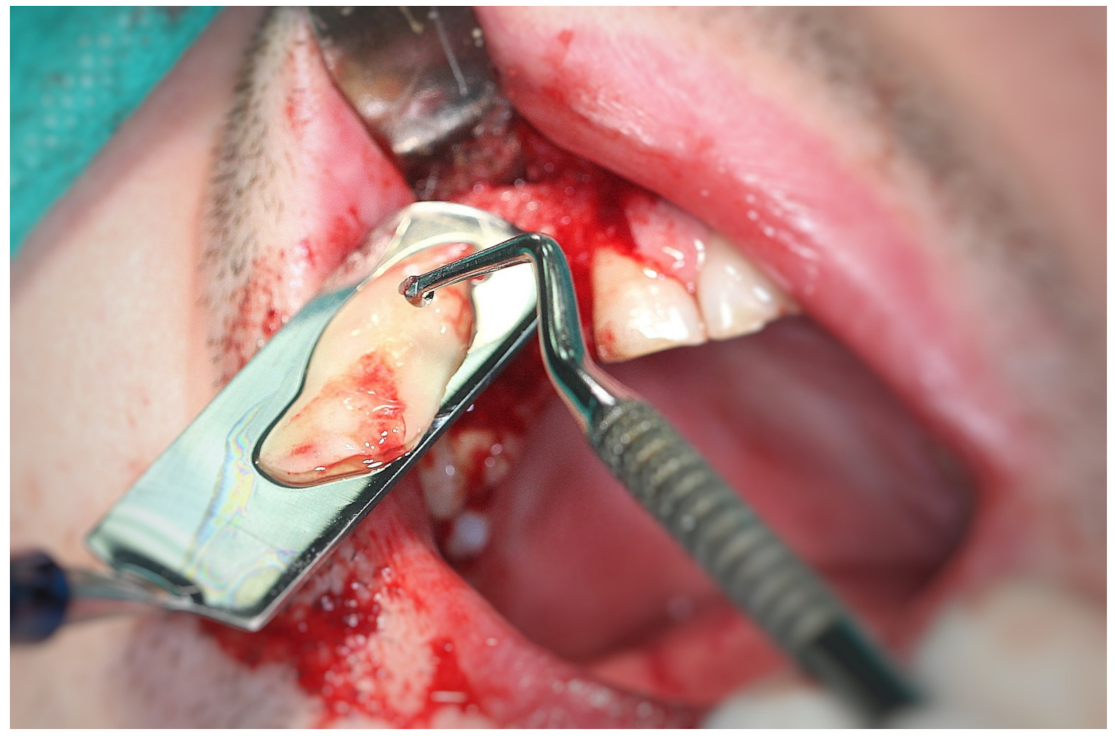

3.2. Surgery

- Tooth after grinding;

- Tooth after 10 min immersion in cleanser (sodium hydroxide solution with 20% ethanol);

- Tooth after immersion in phosphate-buffered saline;

- Heterogenous bone substitute (comparative study);

- Patient’s own soft tissue (comparative study);

- Patient’s own bone (comparative study)-vestibular bone plate.